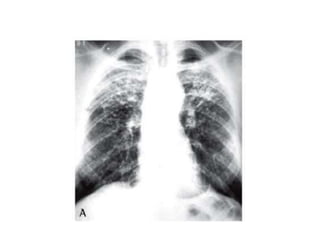

Case 4

Interstitial Lung Disease – A quick

guide

• Umbrella term.

• Consider:

• 1) Idiopathic interstitial pneumonias of which

usual interstitial pneumonia is commonest type

(also known as idiopathic pulmonary fibrosis)

• 2) Interstitial lung disease of known cause –

connective tissue disease, drug related, dusts

which may be organic or inorganic.

• 3) Granulomatous interstitial lung disease –

sarcoidosis.

Interstitial Lung Disease– A quick guide • Umbrella term. • Consider: • 1) Idiopathic interstitial pneumonias of which usual interstitial pneumonia is commonest type (also known as idiopathic pulmonary fibrosis) • 2) Interstitial lung disease of known cause – connective tissue disease, drug related, dusts which may be organic or inorganic. • 3) Granulomatous interstitial lung disease – sarcoidosis.